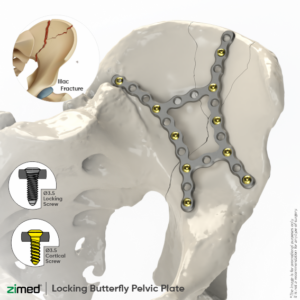

Locking Butterfly Pelvic Plates